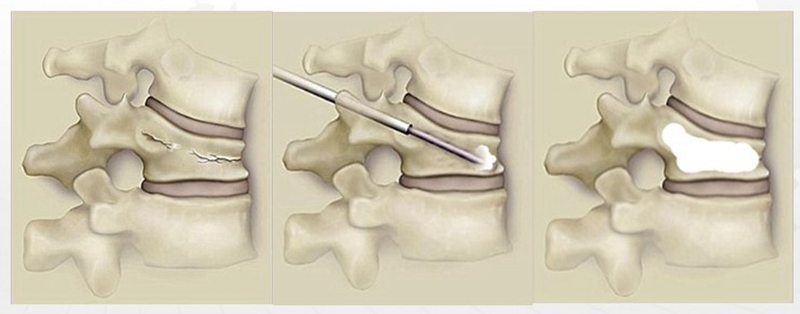

PKP的优点较PVP而言,可以有效恢复部分伤椎高度,改善后凸畸形,同时术中球囊扩张椎体后,为骨水泥灌注形成一个低压环境,减少了渗漏风险。缺点在于手术时间较PVP有所延长,同时球囊撑开椎体过程中挤压骨折界面松质骨使球囊与椎体间形成致密的松质骨壁,阻碍了骨水泥渗透入骨小梁间隙,从而增加了伤椎再骨折的可能。

PCKP的优势在于术中操作安全、便捷、骨水泥弥散好,渗漏率低。术中穿刺过程中穿刺针以更小的穿刺角度进入椎体内,通过弯角骨钻开腔越过椎体中线,增加了穿刺安全区间,减少了术中医源性穿刺损伤的风险;同时通过弯角球囊的独特设计,可以在椎体中部造成弧形空腔,引导骨水泥在灌注过程中从穿刺对侧开始弥散,沿球囊撑开的弧形空腔充分灌注,达到单侧穿刺、双侧弥散的效果,有效降低了骨水泥渗漏风险。